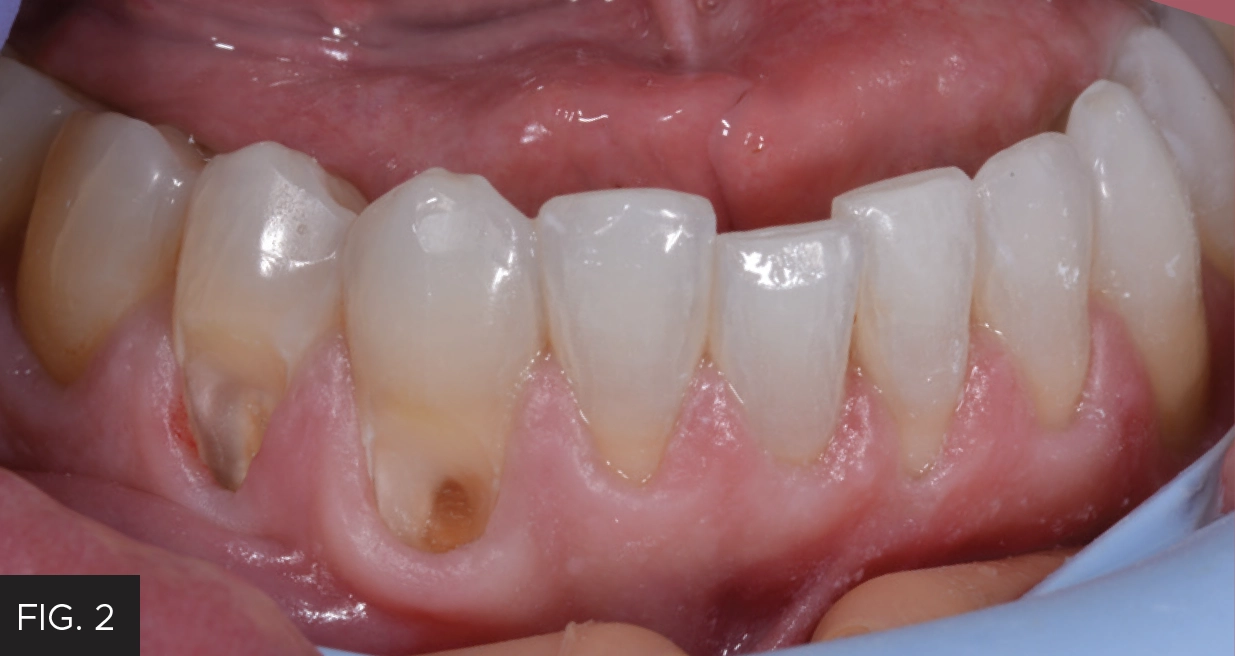

This case report of restorations on teeth #27 and #28 illustrates the extent to which decay can exist subgingivally associated with existing Class V resin restorations. (FIG. 1) To gain access for caries removal and provide ideal conditions for the placement of a bonded full-thickness restoration, the tissue must be either repositioned or removed. The options to manage the gingival tissue involve either a full-thickness flap surgical approach to reposition the tissue or a more conservative option with an electrosurgery unit or a laser. The decision in this case was to use the Bluewave™ Soft Tissue Diode Laser (Clinician’s Choice®), which is a portable 5W 810nm soft tissue laser. The 810nm wavelength is highly absorbable by hemoglobin and melanin, resulting in minimal bleeding, and allows for rapid healing of the wound. The Bluewave diode laser is very cost-efficient, lightweight, battery operated, and portable to easily move between operatories. The unit occupies a small footprint of counter-space and the laser handpiece is held securely in place with a magnetic cradle for increased protection against accidental dislodgement and breakage.